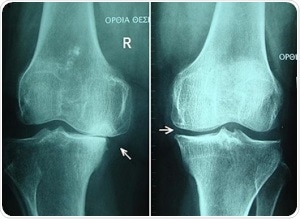

![Bone cross-section by Pbroks13 [CC BY 3.0], via Wikimedia Commons](https://www.appetitewellbeing.com/image-handler/picture/2018/12/2.jpg)

Bone cross-section by Pbroks13 [CC BY 3.0], via Wikimedia Commons

Recent studies on osteoarthritis have led to the belief that changes to the subchondral (below the cartilage) bone structures, like thickening of the subchondral plate, are apparent prior to lesions or other symptoms becoming obvious in the cartilage itself.

The study explored numerous significant parameters of bone integrity in bone samples collected from human cadavers. The main parameters were subchondral bone plate thickness, bone mineral density and structural model index that were measured using near-infrared spectroscopy. A dual channel Avantes system combined with the AvaSpec-ULS2048L with the high-sensitivity AvaSpec-NIR256-2.5-HSC was used to record the NIR spectral data.

Spectra were recorded across three wavelength series already recognized for penetrative capabilities in living tissue. This is called the biologic or therapeutic optical window. Firstly, the window covered the range 650-950 nm, then, from 1100-1350 nm, and lastly, the biologic window studied was 1600-1870 nm. This data was correlated against micro-computed tomography results of the same bone samples using partial least squares regression multivariate technique.

Findings showed that an important role was played in the relationship between optical response and subchondral bone properties due to the wavelength-dependent penetration of light into osteochondral samples. The strongest correlation and lowest error rate against the tomography results was identified in the first optial window; λ 650-950 nm. This presents the highest potential for adaptation into arthroscopy standards of care.